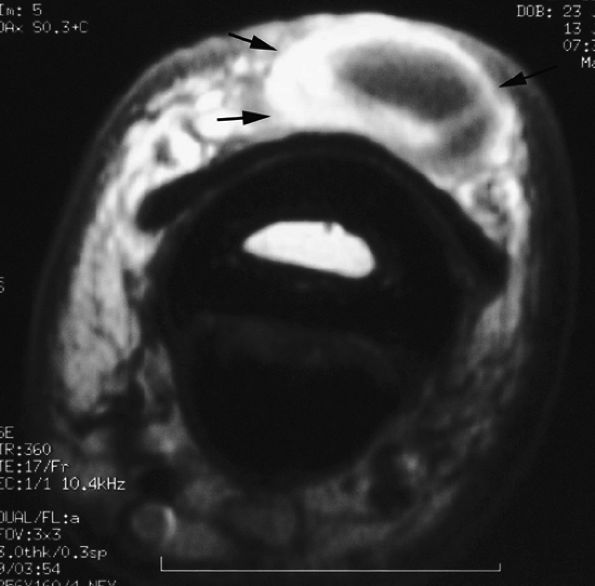

FIGURE 11.128 ● Vascular-type glomus tumor (asterisk) of the nail bed with the most common signal characteristics. (A) Axial T2-weighted image. T1-weighted images before (B) and after (C) injection of gadolinium. (D) MR angiogram. The tumor is located on the midline with an underlying bone erosion (arrowheads). The signal is high on T2-weighted images and slightly high on T1-weighted images. There is strong post-contrast enhancement on T1-weighted images and MR angiography.